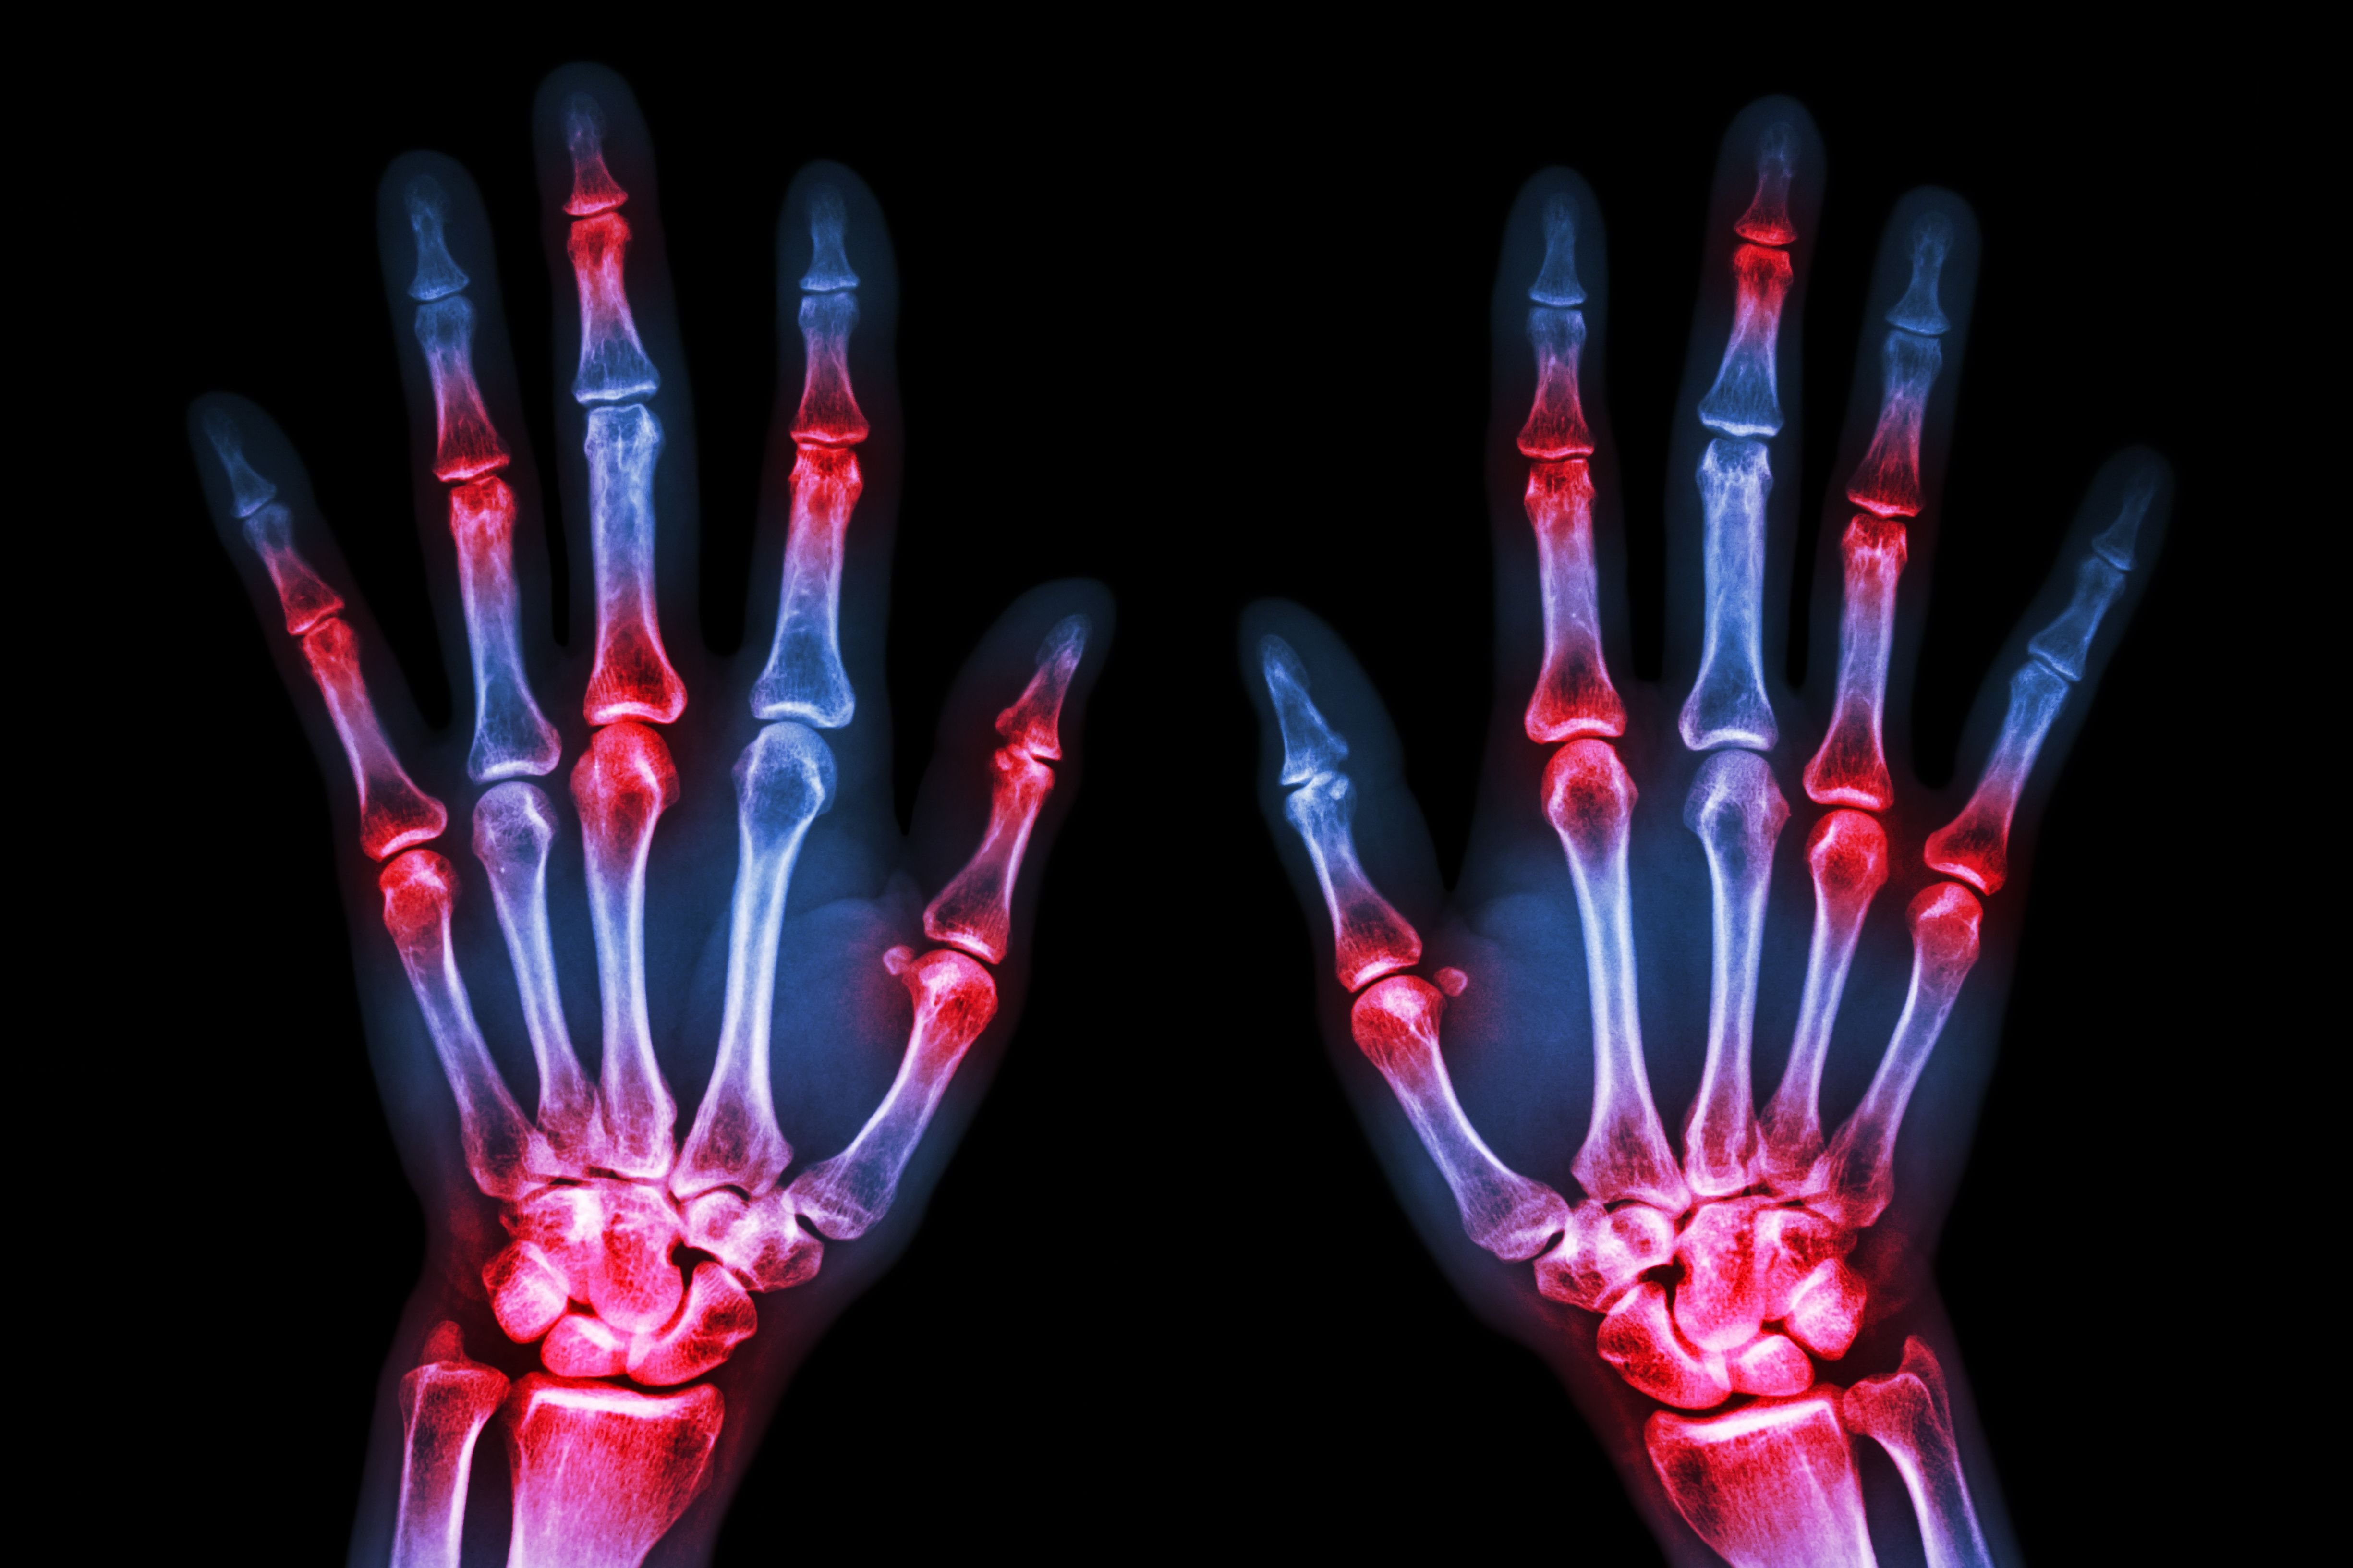

(Vienna, 21 February 2020) Two indices for assessing disease activity in rheumatoid arthritis that have been developed at MedUni Vienna are increasingly regarded as the gold standard in clinical practice and in scientific applications. The "Simplified Disease Activity Index" and the "Clinical Disease Activity Index" record changes, allow a clear distinction between low, moderate and high disease activity, include remission criteria and are simple to use in everyday clinical practice. Most of the revenue generated from copyright royalties is ploughed straight back into rheumatology research at MedUni Vienna.

Daniel Aletaha and Josef Smolen from the Division of Rheumatology of the Department of Medicine III of MedUni Vienna/Vienna General Hospital have been collaborating for years on the research and development of better and simpler instruments for assessing disease activity in rheumatoid arthritis. They developed the "Simplified Disease Activity Index" (SDAI), which is based on the examination of 28 joints, an assessment of disease activity by patient and doctor and measurement of the CRP level. If one were to omit the CRP laboratory value, one then has the even simpler "Clinical Disease Activity Index" (CDAI).

The SDAI and the CDAI reflect disease activity very effectively, record changes, allow a clear distinction to be made between low, moderate and high disease activity, include remission criteria and are easy to use in everyday clinical practice.